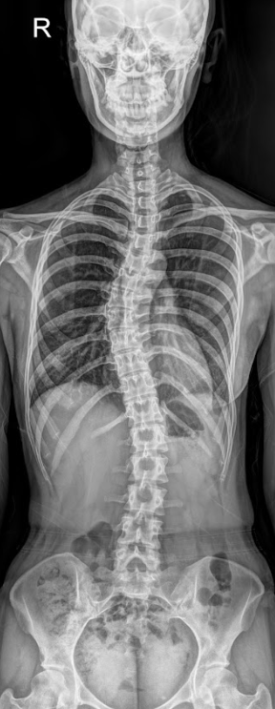

전척추 엑스레이 진단: 환자분께 전척추 엑스레이(경추-흉추-요추-골반대) 촬영을 요청해 척추 배열 상태를 확인합니다.

척추 배열 변화를 통해 자율신경에 가해지는 물리적 압박 상태를 추정하고

진료 후 척추 배열이 정상에 가깝게 개선되는 것을 시각적으로 확인하죠.